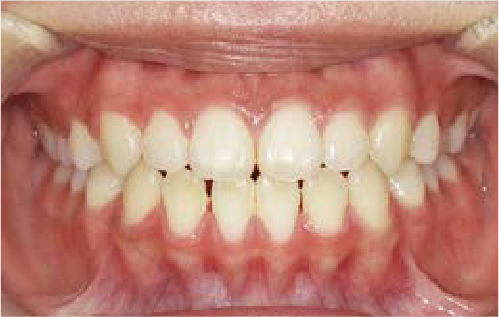

After

前歯のすき間や歯並びの乱れが見られ、普段の生活の中で、無意識に舌を押しつけるクセや飲み込み方のクセが確認されました。

治療を終えて

装置をしっかり使うことで、あごの位置が整い、舌の正しい位置や動きが戻り、ほっぺたやくちびるの筋肉の使い方も改善されました。その結果、歯並びが整いお口の機能も良くなりました。もちろん非抜歯での治療です。

主訴・治療内容 他院で抜歯のうえ、ブラケット矯正を勧められたが、できれば歯を抜かずに治療したいとの要望で来院されました。

治療期間 5年4ヶ月

費用 495,000円(税込)